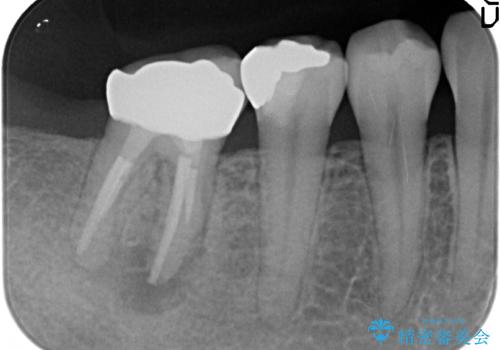

- 銀歯がしみることを主訴に来院されました。

銀のつめものを除去したところ、大きなう蝕を認めました。

咬合力が強いため、割れる心配がなく強度の高いPGA(ゴールド)インレーをご希望されました。

治療後はしみなくなり、違和感のない自然な咬み心地にご満足頂けました。